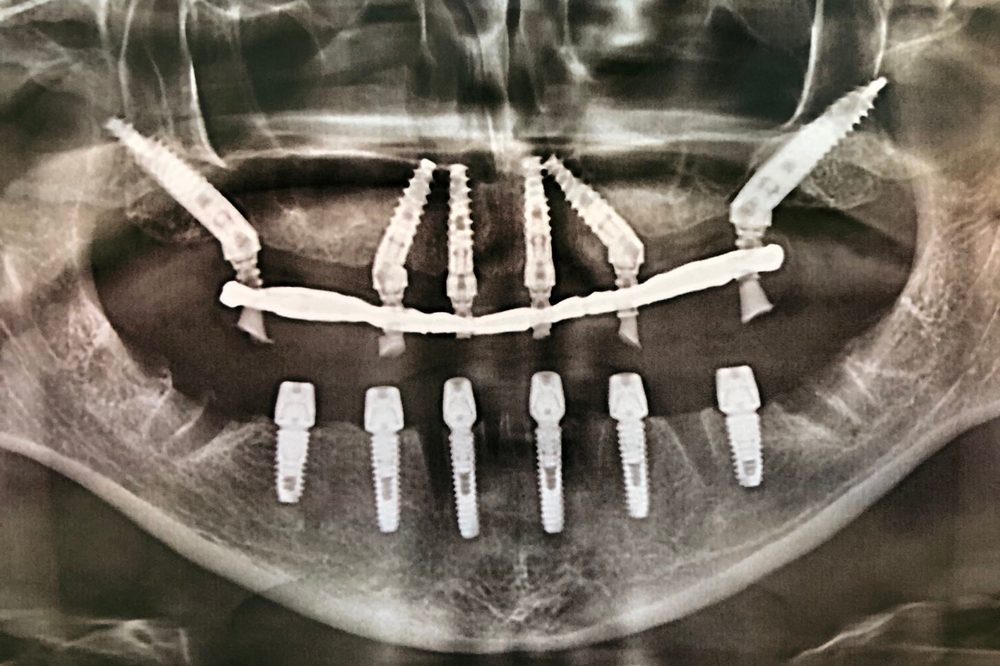

Кейс №1 - Установка несъемных протезов на обе челюсти за 5 дней

02 Сентября 2020 Имплантация зубов по методике All-on-6

Изучив данные 3D-исследования, которые пациентка прислала через интернет, доктор предложил провести протезирование верхней и нижней челюстей в кратчайшие сроки при помощи методики All-on-6 (все на 6-ти). Во время операции были удалены старые протезы, оставшиеся зубы, установлены 6 имплантатов на верхней и 6 имплантатов на нижних челюстях, и за 5 дней были изготовлены и фиксированы несъемные эстетичные протезы на обеих челюстях.